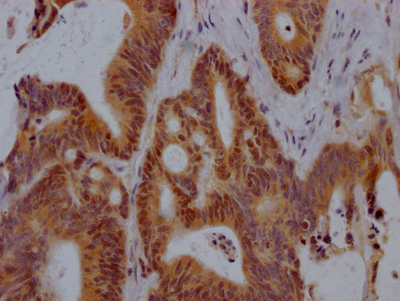

The image on the left is immunohistochemistry of paraffin-embedded Human cervical cancer tissue using CSB-PA297945(KRT13 Antibody) at dilution 1/35, on the right is treated with fusion protein. (Original magnification: ×200)